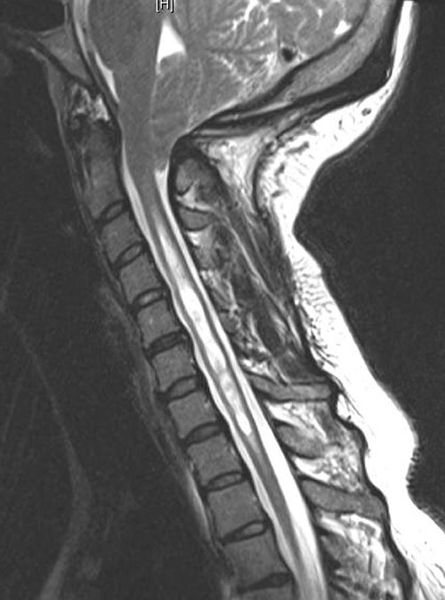

MRI의 발달로 과거보다 최근에 발생빈도가 높게 보고 되고 있습니다.

척추 부위에 MRI 검사를 시행하여 척수의 병변을 확인하게 됩니다.

또한 MRI에서 보이는 척수공동증에 대해서 다른 원인 요인이나 현재 증상에 대해서 감별 및 이상 정도를 확인하기 위해 뇌의 MRI나 유발전위 검사나 근전도 검사와 같이 신경학적 검사도 진행하게 됩니다.